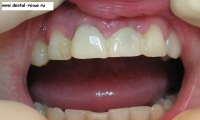

21. Примерка коронок после перебазировки, коррекция окклюзии.

23. Вид зафиксированных на абатментах временных коронок. Они присоединены к соседним зубам с помощью светоотверждаемого композита.

24. Временные коронки после установки.

29. Ткани десны спустя неделю после оперативного вмешательства. Жалоб нет, фиксация коронок хорошая.

30. Улыбка пациента спустя неделю.